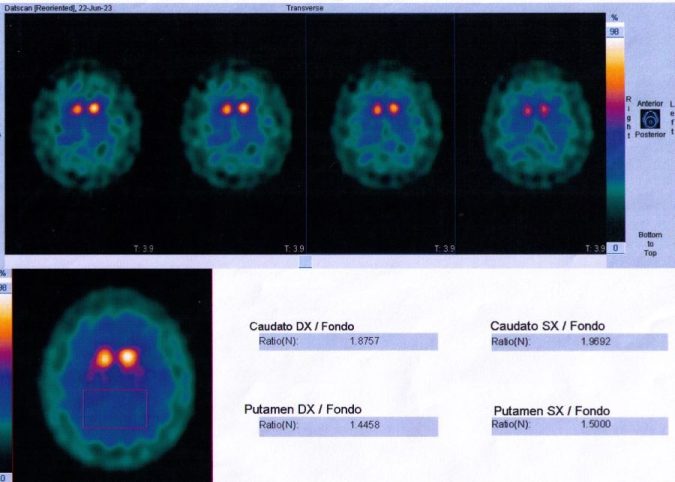

“I also tried vitamin B1 and B3 supplements to ease the side effects induced by my Parkinson’s, and I must admit that when I take them, I feel better. However, the form of Vitamin B3 I use is the water-soluble molecule contained in an effervescent tablet. Of course, if a more advanced molecule of vitamin B3 could stop the progression of Parkinson’s, I would be extremely happy. But the new study is at the beginning, and the results showed to be different from patient to patient,” Journalist Rosalba Mancuso said. She was indeed diagnosed with Parkinson’s in 2023 (see the image of her Brain Scan).

Featured image: Courtesy of Rosalba Mancuso